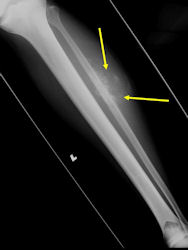

Skip metastases: metastases within the same bone, or across the joint in the adjacent bone, as the primary osteosarcoma

- spread via intraosseous or transarticular venous system within the bone

- rare; may occur without any evidence of pulmonary metastases

- traditionally associated with poor prognosis, although recent reports may suggest otherwise

- detection of skip metastases is important for surgical planning; occasionally, presence of skip metastases may dictate that the entire bone be surgically removed

MRI: Osteosarcoma of distal femur with skip metastasis to proximal femur

- detecting skip metastases

- Entire bone and adjacent joint should be visualized